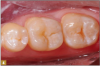

The conservative nature of these preparations allows complete restoration with a flowable Giomer. The teeth were etched with 37% phosphoric acid for 15 seconds (Figure 5). After thorough rinsing, a universal bonding material was applied with several coats and air thinned (Figure 6). Air thinning is important to remove the solvents and to provide and thin the film. The surface at that point should be visibly shiny, signifying complete, effective preparation coverage by the bonding agent (Figure 7).

A 0.5 to 1.0 mm layer of Giomer flowable with self-leving properties and low flow was applied to cover the dentin; it was then light-cured for 15 seconds (Figure 8). Uncured resin weakens the restoration at the tooth-restorative interface and may be a pulpal irritant resulting in patient discomfort. It is therefore prudent that the layers closest to dentin be polymerized to their greatest potential. A thin layer of material over the dentin provides the best potential for ultraviolet light-induced polymerization before thicker, harder-to-penetrate layers are added. Sealing the dentin with a thin layer of well-cured Giomer flowable allows ionic release at the restoration-dentin interface. The bond of restorative materials deteriorates with time from many factors, such as enzymes, acids, and mechanical forces, which may decrease sensitivity while increasing restoration longevity. Flowable was then applied to complete the contour of the restoration, and it was then light-cured (Figure 9). The occlusion was checked with articulating paper, adjusted, and polished with a rubber cup (Figure 10). The result was a conservative, esthetic, regenerative restoration.

Fig 6. Giomer was applied with a microbrush before air drying and then light-curing.

Figure 6

Fig 7. A bioactive flowable composite was self-leveled into grooves, covering the dentin with a thin layer about 2 mm deep.

Figure 7